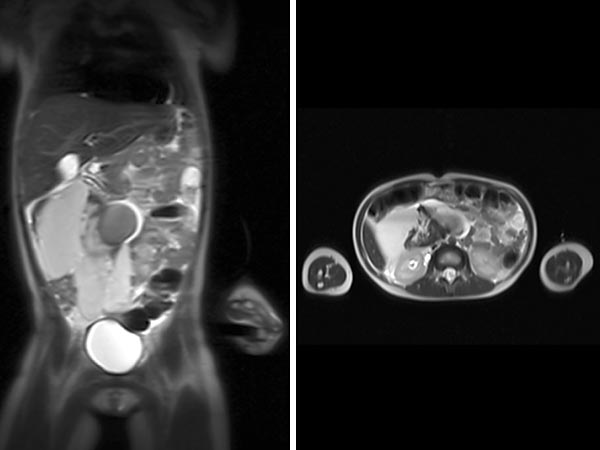

The first case is a 5-year-old girl with distended abdomen. On coronal and transverse T2-weighted, fat-suppressed MRI, an extensive macrocystic lymphatic malformation is visible with large cysts displacing the bowel.

Fat-saturated, T2-weighted MRI in three planes reveals the cause: retroperitoneally located giant cysts due to a macrocystic lymphatic malformation.